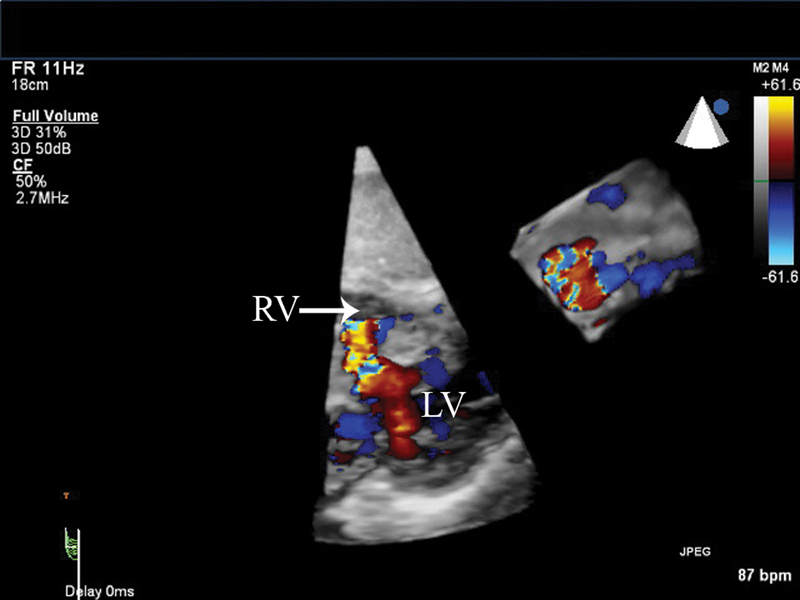

فحوصات تشخيصية لبعض امراض القلب والشرايين التاجية